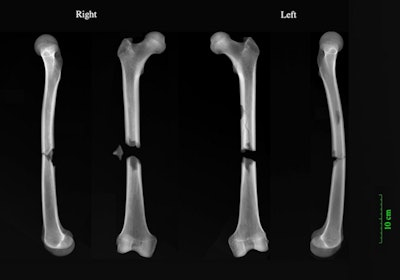

"The friar had complete fractures halfway up both his femurs," said Dittmar in a press release. "Whatever caused both bones to break in this way must have been traumatic, and was possibly the cause of death. Our best guess is a cart accident. Perhaps a horse got spooked and he was struck by the wagon."